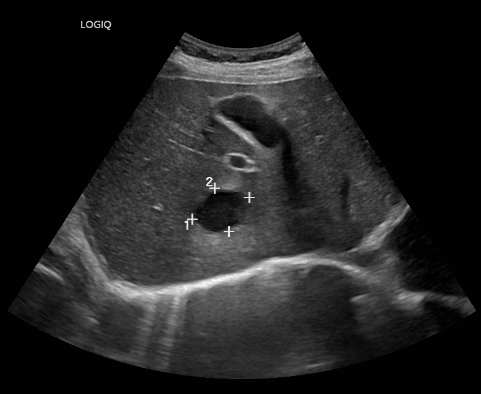

前段时间会诊了一名因为发热入院的老年患者,住院期间做胸部CT发现肝占位,因为既往有肺癌手术史,不排除肺癌肝转移,所以请肝胆外科会诊。经过肝脏超声等进一步检查(图1),考虑为肝脓肿可能性大,给予抗感染治疗后症状缓解后出院,5个月后复查,肝脓肿明显缩小(图2)。

图1:超声可见肝脓肿范围3.3cmx2.5cm